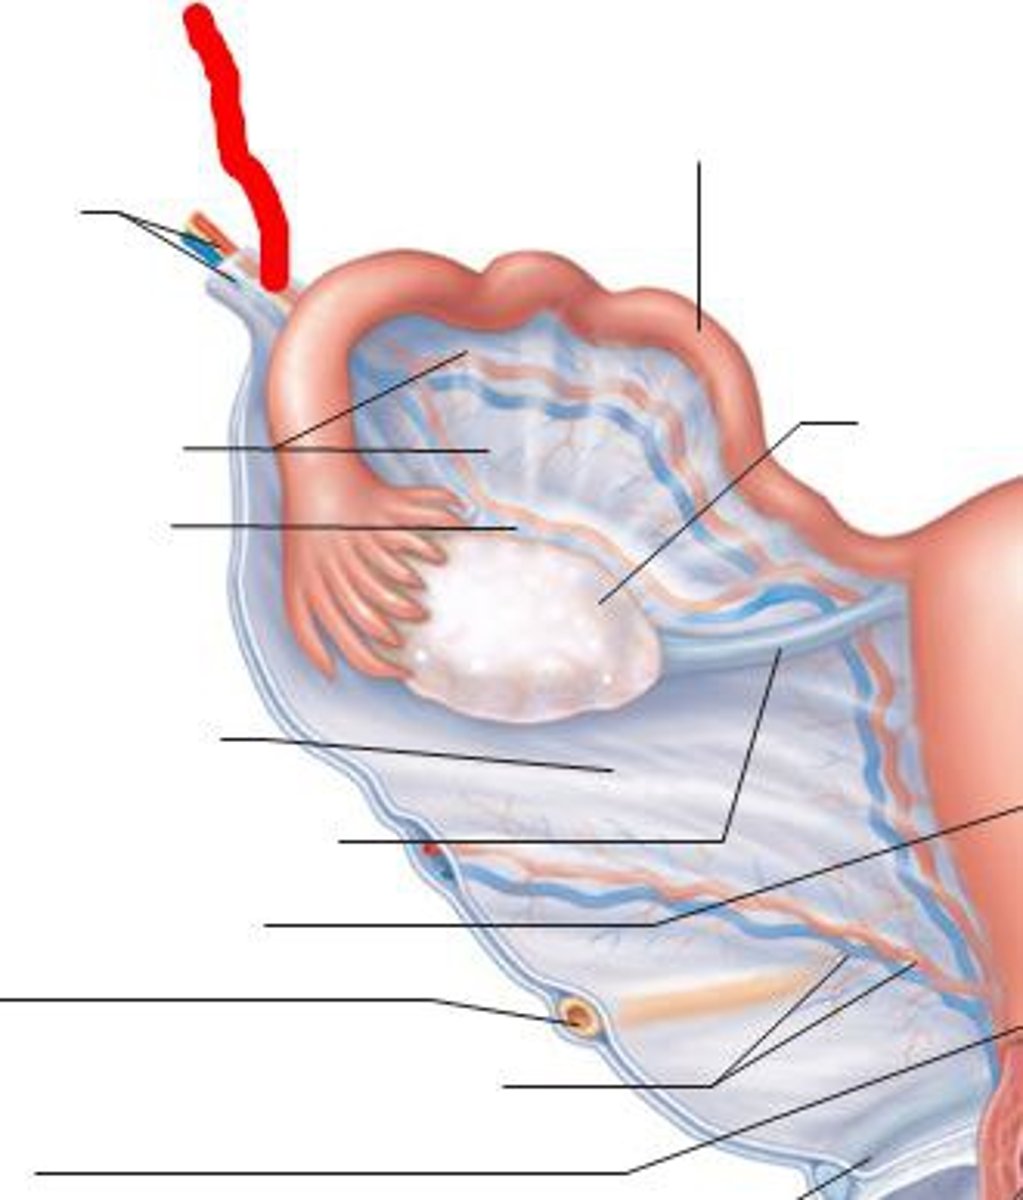

ovary

uterine tube

fimbria

infundibulum

corpus albican

corpus hemorrhagicum

corpus luteum

mature follicle

antrum

corona radiata

cumulus oophorus

follicular fluid

granulosum cells